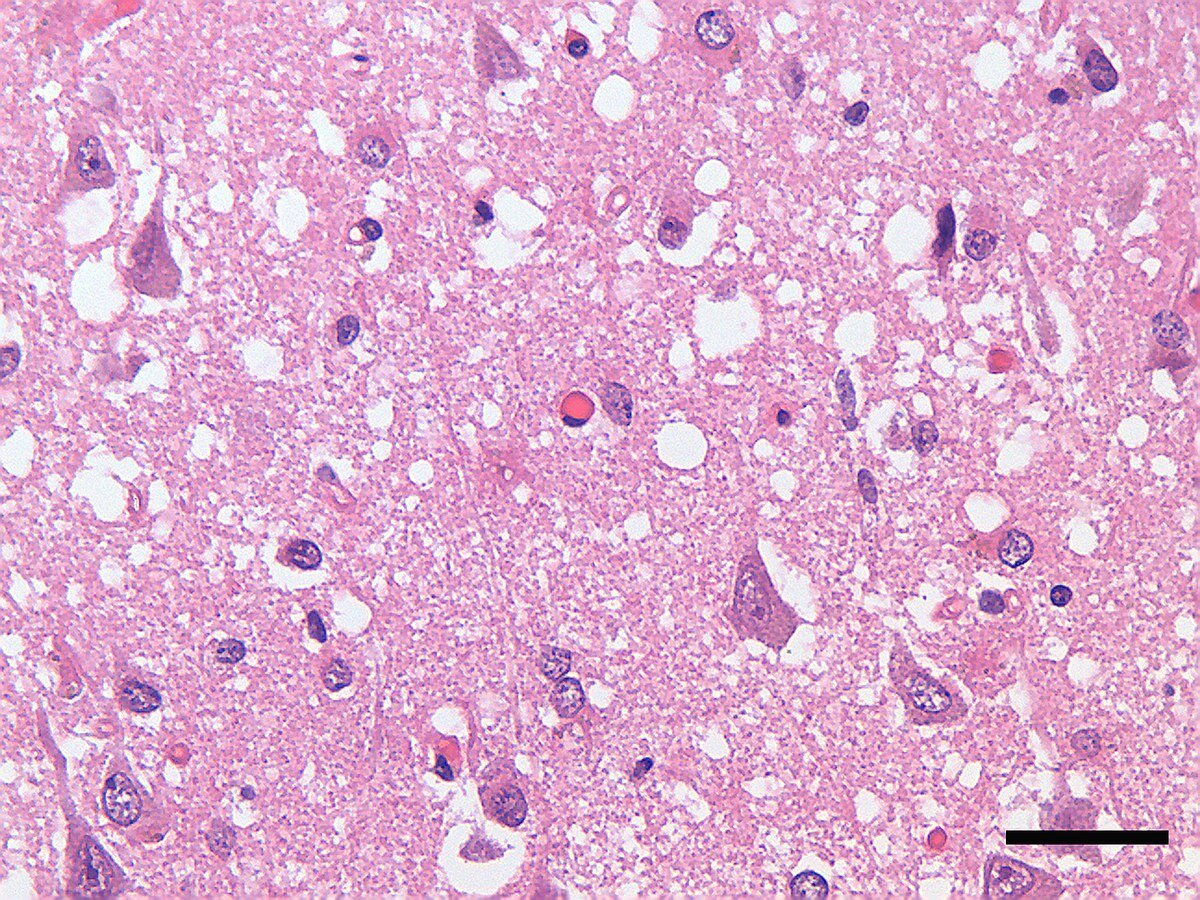

Препарат ткани мозга при БКЯ

Эти меры были введены поздно: в 1996 году была зарегистрирована смерть 11 человек от нетипичной болезни Крейтцфельдта-Якоба. И с помощью опытов на мышах удалось доказать: новый вариант болезни и «коровье бешенство» - это одно и то же. До 2004 года выявили ещё 158 случаев, затем число заболевающих пошло на убыль: профилактика сделала своё дело. Лучше поздно, чем никогда.